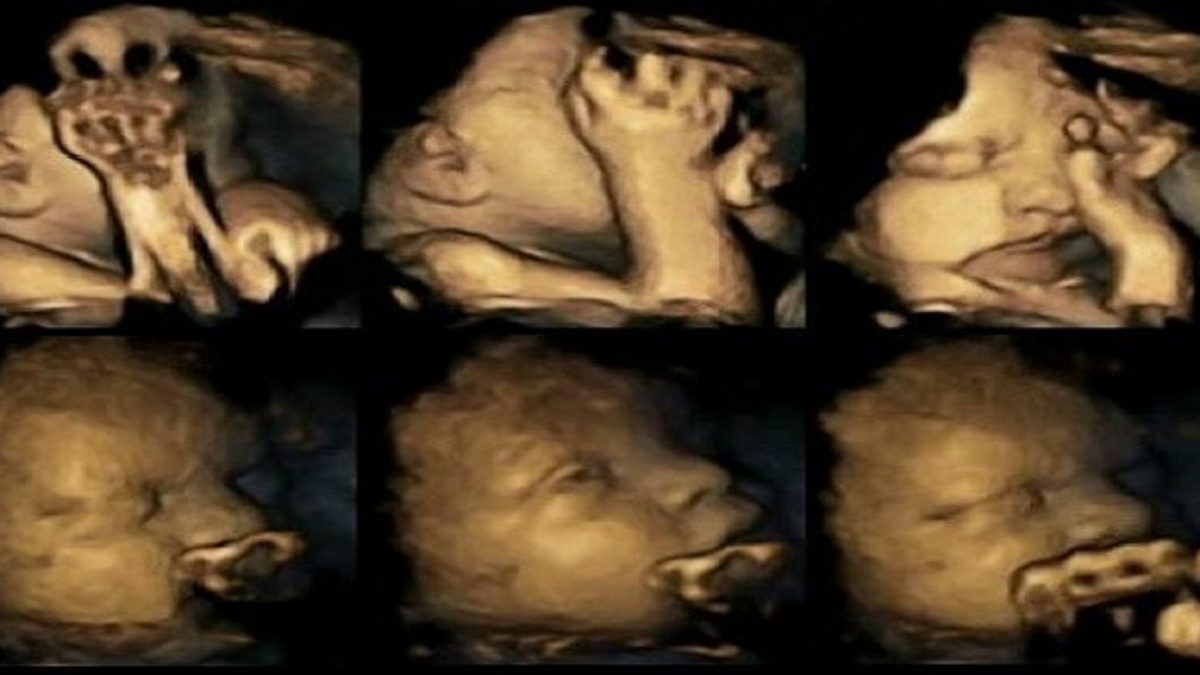

Yeni yapılan bir araştırma, hamile kadınlarda sigara kullanımının zararlı etkilerine daha fazla ışık tutuyor. 4D ultrasonla yapılan taramalarda, rahimdeki fetusun minik hareketleri gözlemlendi.

Fetuslar geliştikçe, genellikle ağızlarını hareket ettirirler ve kendilerine dokunurlar ve kollarını kontrol edebilme yetisi kazanırlar. Bebeklerin büyümesini gözlemleme ile bilimciler rahimdeki fetusun dakika düzeyindeki hareketlerinin değerlendirilmesiyle potansiyel problemlerin saptanabileceğine inanıyorlar. Araştırmanın hamile kadınları sigara içme alışkanlığına son vermeleri noktasında tetikleyici olacağı ümit ediliyor.

Yukarıdaki görüntü grubu sigara kullanan annenin rahmindeki fetusu gösteriyor. Aşağıdaki görüntü grubu ise hamilelik sırasında sigara kullanmayan annenin rahmindeki fetusun görüntüsü.

[su_spacer size=”5″]Dr. Nadja Reissland, 20 anne adayının hareketli 4D ultrason taramaları üzerinde çalıştı. Anne adaylarının sigara kullanan dördünde, fetusun gelişiminin 24., 28., 32. ve 36. haftalarında binlerce minik hareketi kaydedildi.Middlesbrough ‘da James Cook University Hospital ‘da yapılan çalışmada, hamileliği sürecinde sigara kullanan bu dört anne adayının rahimlerindeki bebeklerin yüzlerine daha sık dokundukları görüldü.

Dr. Reissland’in sonuçları –kendisi çalışmayı daha geniş bir örneklemde tekrarlamayı umuyor– sigara kullanan annelerin bebeklerinin merkezi sinir sistemi gelişimini yavaşlatabileceğini ortaya çıkardı.